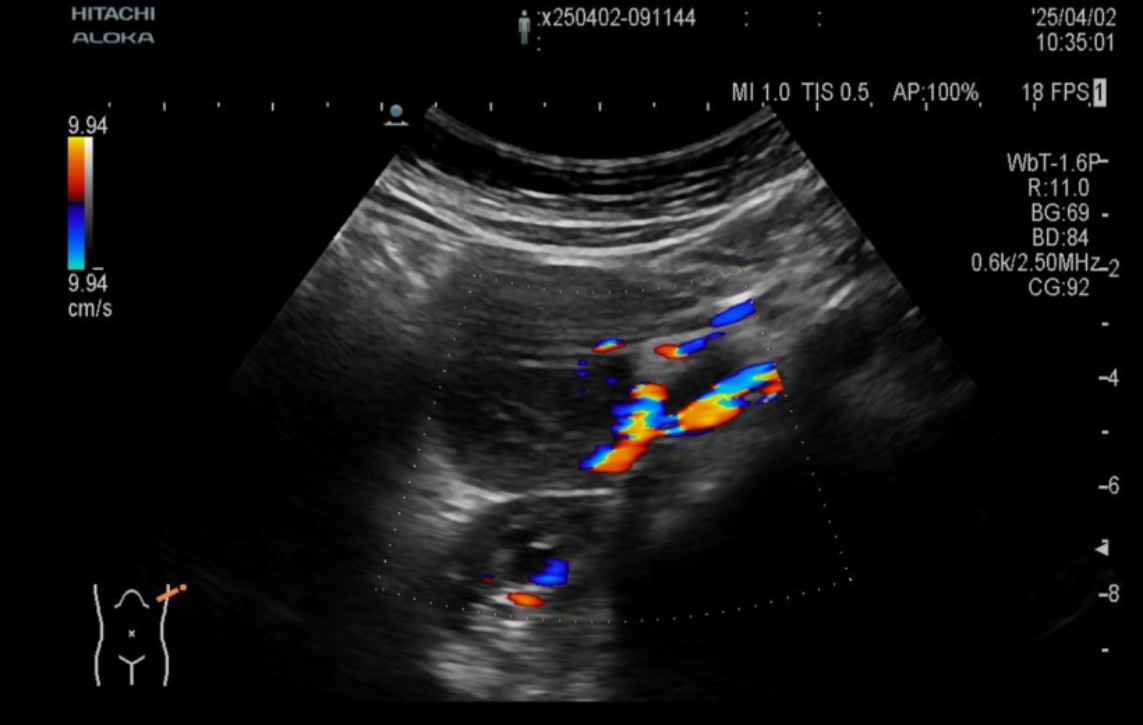

患儿男,年龄11岁3个月。因“阵发性脐周腹痛1周”于2025年4月1日入我院就诊。患儿腹痛持续时间不等,性质为隐痛,平素无发热、头晕、头痛,无恶心、呕吐,无腹泻便秘、小便发黄等症状,体重、体力无明显下降。既往贫血3年,定期复查血常规:血红蛋白90~105 g/L波动,长期补充铁剂无改善。否认相关病毒感染史、传染病史等其他病史。体格检查:神志清,精神可,面色皮肤苍白,指甲床苍白,无皮肤出血点及瘀斑。颈部、腋窝、腹股沟等全身浅表淋巴结无明显肿大,腹平坦,腹软不胀,未见胃肠型及蠕动波,移动性浊音阴性,右下腹压痛,无反跳痛,余腹无压痛及肌紧张,肝脾肋下未触及,Murphy阴性,未触及明显肿物,肠鸣音4次/分。实验室检查:血常规:血红蛋白85 g/L,血小板740 × 10^9/L,C反应蛋白25 mg/L,肝功能:白蛋白29.7g/L,白细胞介素-6:66.31 pg/ml,免疫球蛋白测定(血):抗O:>1770 IU/ml,血沉:111 mm,EB病毒衣壳抗原IgA 6.19 AU/ml,EB病毒衣壳抗原IgG > 50 AU/ml,EB病毒核抗原IgG > 50 AU/ml,HHV-8:阴性,IgG4 25.12 g/L。肿瘤标志物甲胎蛋白、癌胚抗原、糖链抗原199、神经元特异性烯醇化酶等检查指标均在正常参考范围内,Coombs实验阴性。完善超声检查:腹腔内右肾前方水平见6.0 × 4.3 × 5.6 cm低回声团块,分叶状,边界清,似有包膜,余肠系膜根部关系密切,考虑系膜来源或淋巴来源(图1)。下腹部CT平扫 + 增强提示:腹膜后可见软组织肿块影,边界清,大小约46 mm × 55 mm,增强扫描可见均匀强化,肿块周围及腹腔可见多发稍肿大淋巴结影,考虑腹膜后占位,Castleman?(图2)

Figure 2. Enhanced CT reveals a uniformly enhanced soft tissue mass in the retroperitoneum

2. 增强CT提示腹膜后均匀强化软组织肿块